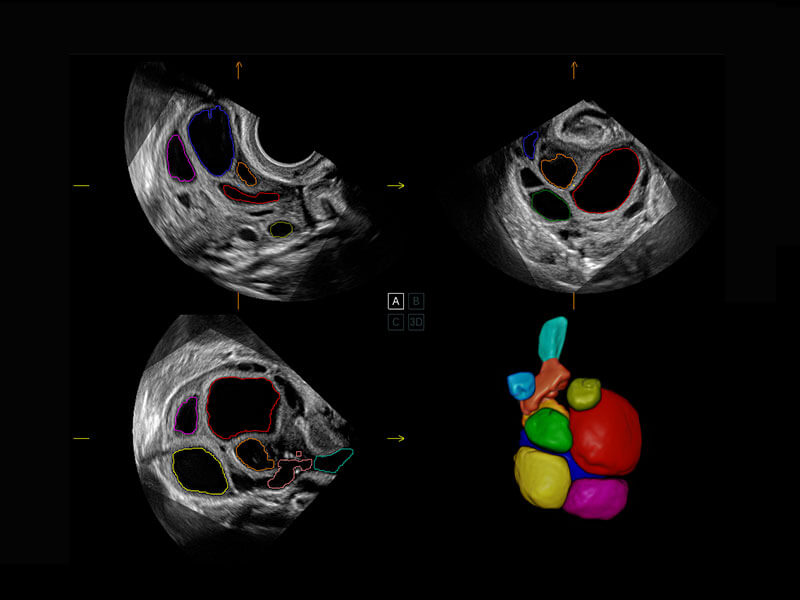

胎心筛查

P60搭载一系列胎儿心脏成像技术,实现精细的胎儿心脏评估。

• 四腔切面

• 四腔心血流

• 右室双出口

• 胎心容积成像